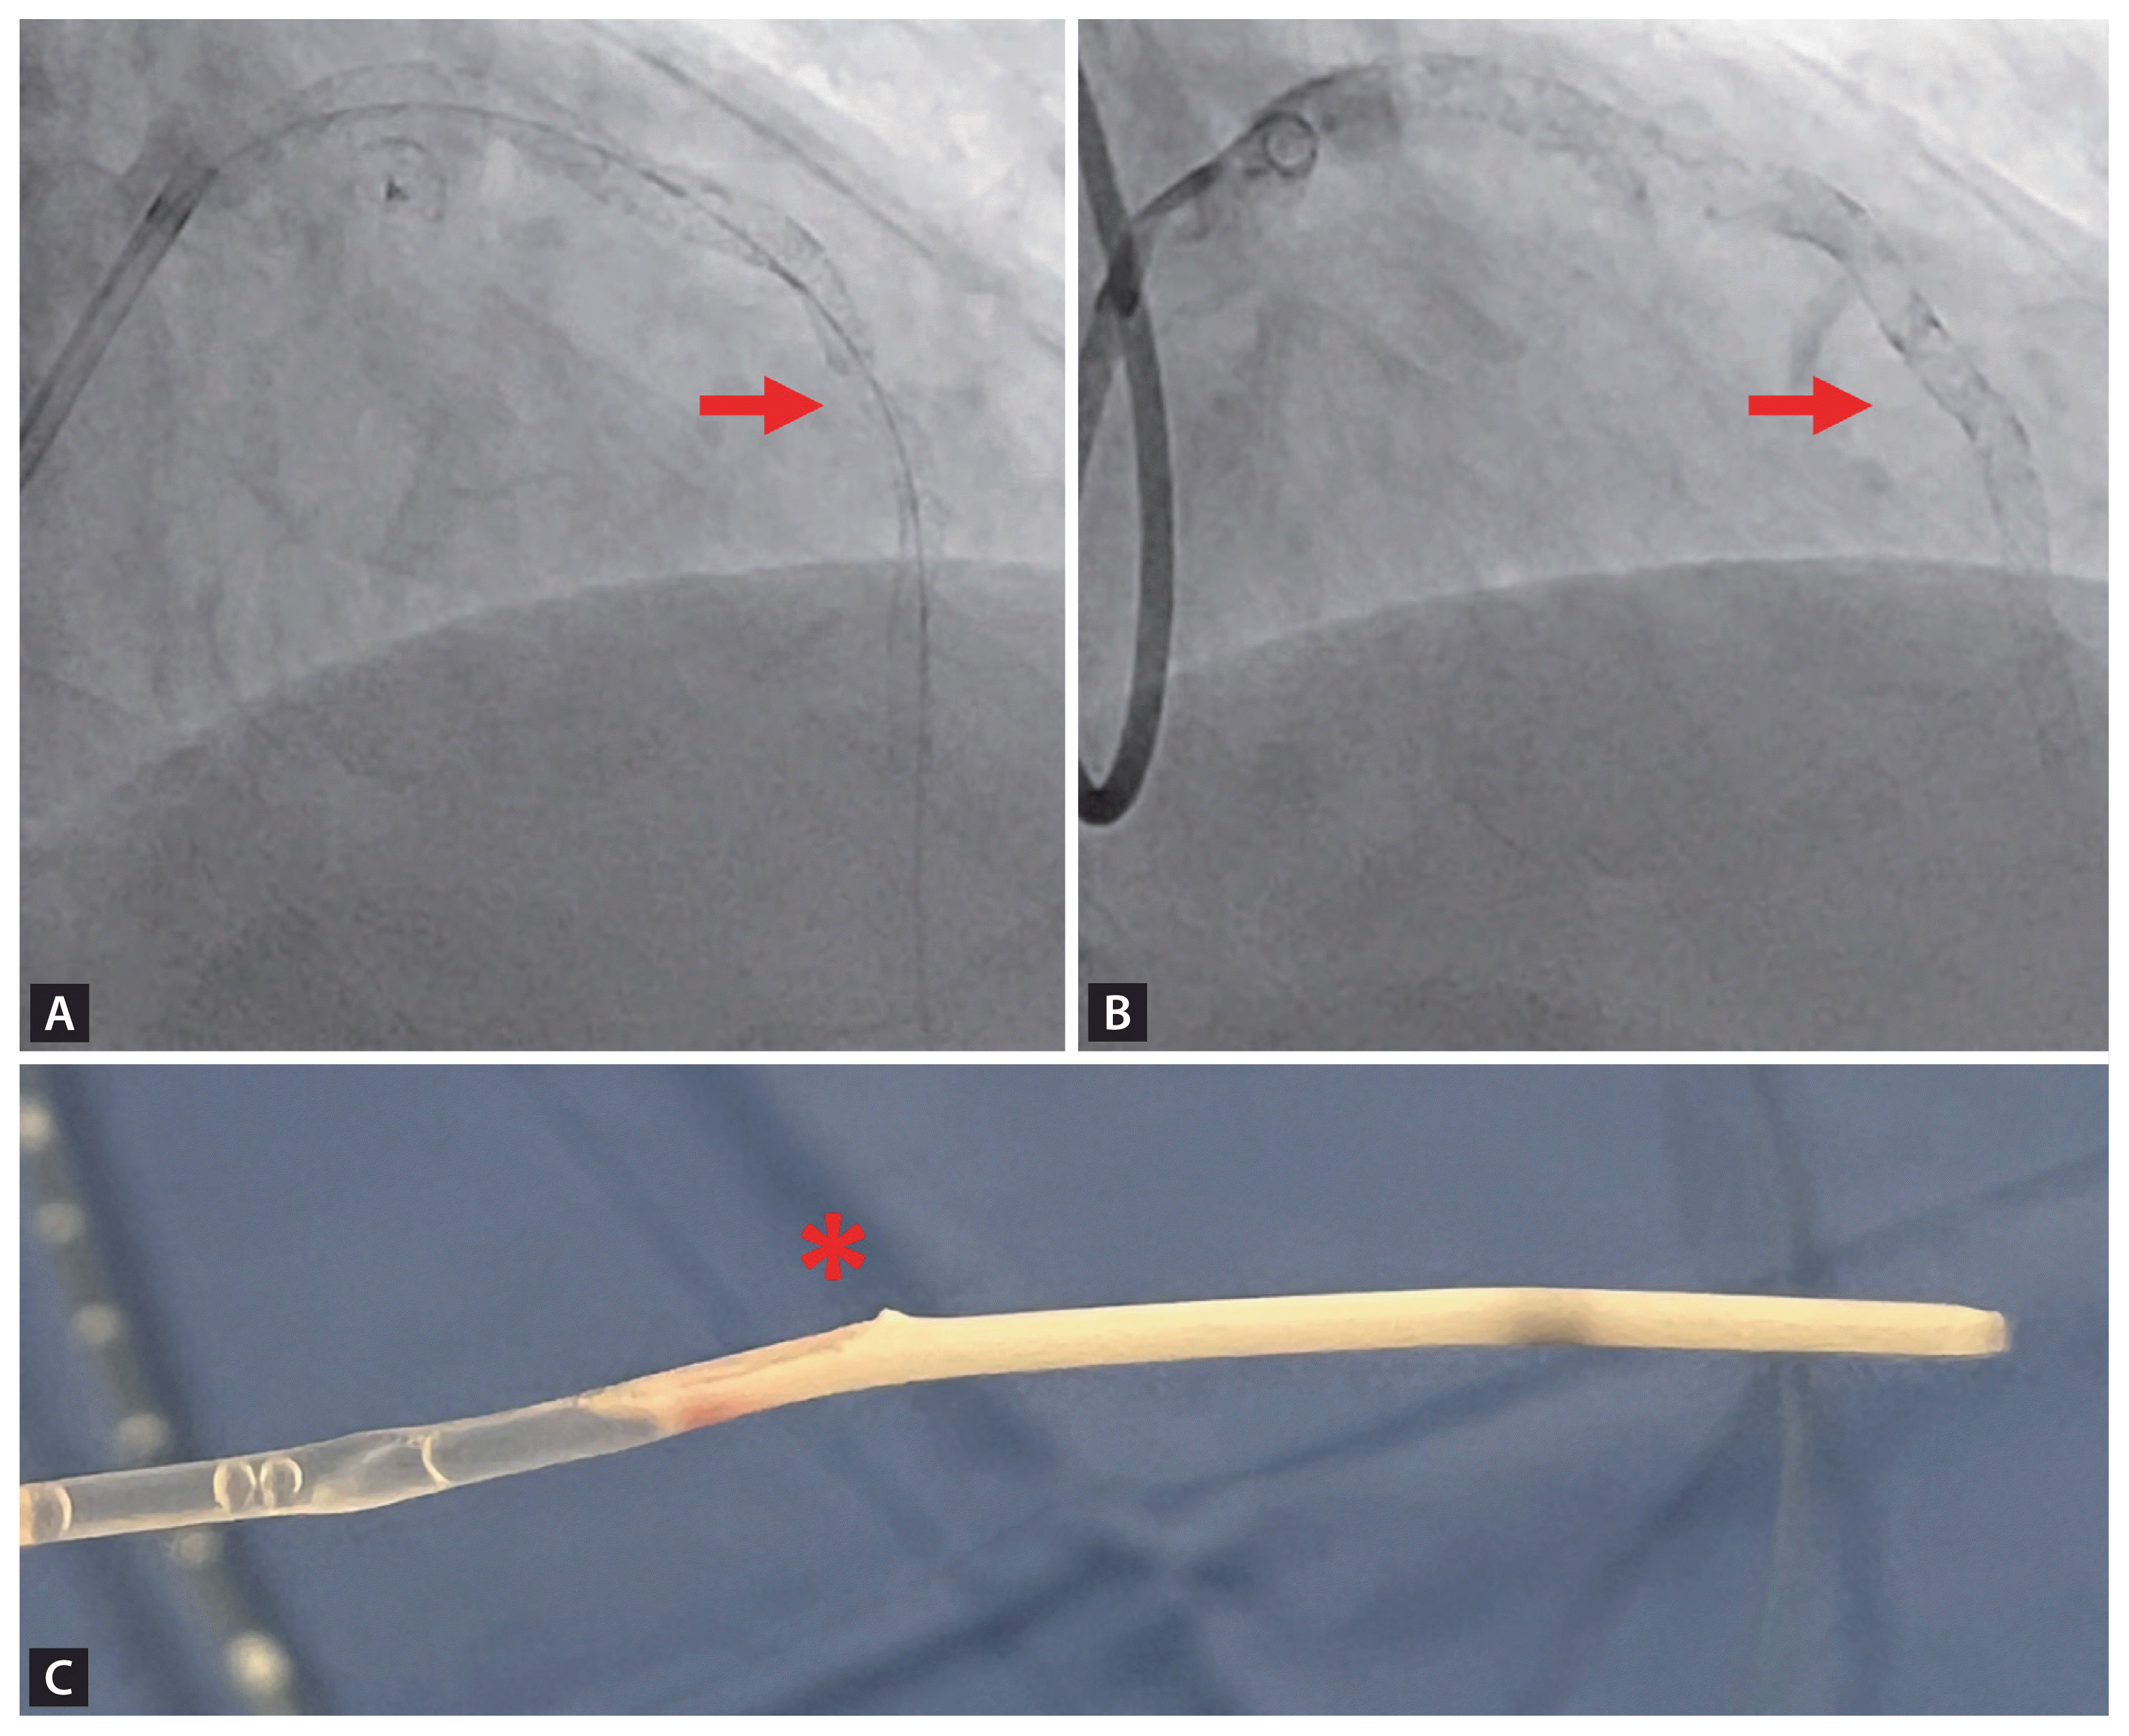

A 65-year-old male visited the emergency department and presented as anterior ST-elevation myocardial infarction (STEMI). Coronary angiography (CAG) showed severe stenosis (90%) in the proximal-to-mid segment of the left anterior descending artery as the culprit lesion. Despite severe tortuous the lesion, two drug-eluting stents (DES) (Synergy, 3.5 × 38 mm and 2.75 × 38 mm) were successfully implanted. Intravascular ultrasound (IVUS) was performed pre-optimization to assess stent apposition; however, catheter entrapment occurred at the proximal stent distal site during IVUS probe withdrawal. Forced extraction resulted in stent deformation with partial strut stripping, confirmed by repeat angiography. To address this complication, an additional stent (Synergy, 3.0 × 12 mm) was deployed (Fig. 1).

Figure 1

(A) After forcible withdrawal, fluoroscopy showing the deformity of stent strut (red arrow). (B) Additional stenting was performed to resolve the deformity (red arrow). (C) A widened wire exit opening of the catheter was identified (red asterisk). It became stuck in the bent stent strut, resulting in catheter entrapment.